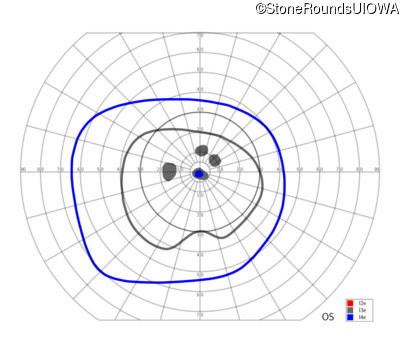

Congenital Stationary Synaptic Dysfunction (IA2g)

Congenital Stationary Synaptic Dysfunction (IA2g)

| Congenital Stationary Synaptic Dysfunction | CABP4 | Arg49Stop CGA>TGA | IVS1+1 G>T | AR |